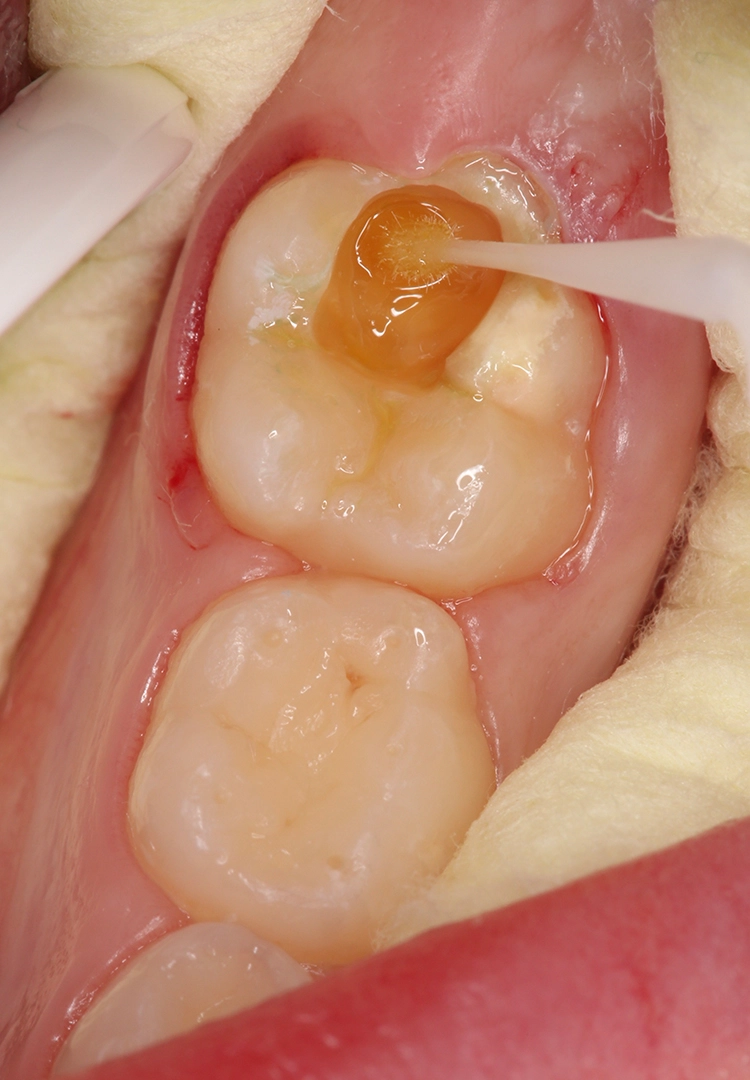

Glasionomerzement

Bekes/BoukhobzaAbb. 4: Abdeckung eines MIH-Molaren mit einem Glasionomerzement.

Glasionomerzemente sind ideal zur initialen und provisorischen Abdeckung von durchbrechenden Zähnen und zur Vermeidung eines weiteren Zahnhartsubstanzverlustes (Abb. 4). Die einfache Handhabung, aufgrund des Wegfalls von Konditionierungsschritten, erleichtert die Anwendung besonders bei eingeschränkter Kooperation des Patienten. Aufgrund der niedrigen Biegefestigkeit und minimalen Abrasionsstabilität eignet sich dieses Material jedoch nicht als definitives Restaurationsmaterial von MIH-Molaren, da gerade bei großflächigen, höckerersetzenden Bereichen keine adäquate Stabilität gewährleistet wäre.

Seit Einführung der ersten Glasionomerzemente in den 1970er-Jahren wird eine vorteilhafte Fluoridfreisetzung durch dieses Material behauptet. Die aktuelle Datenlage zeigt jedoch, dass die Abgabe von Fluoridionen klinisch eine eher untergeordnete Rolle spielt, da diese Wirkung bereits nach einigen Tagen auf ein vernachlässigbares Niveau sinkt [13].